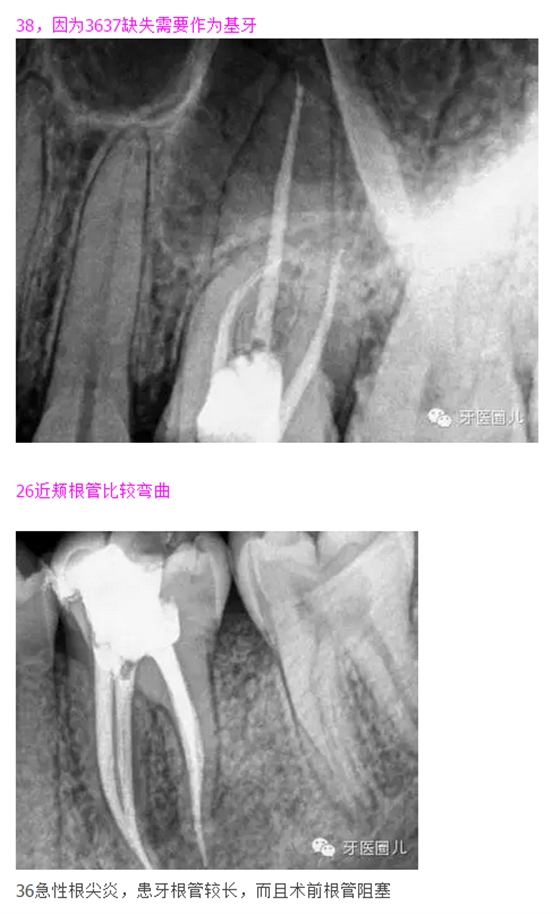

38,因為3637缺失需要作為基牙

這三個病例采用protaper器械,最后一個病例有不足,遠(yuǎn)中舌根根尖2mm有一個嚴(yán)重的向上彎曲,預(yù)備和充填時沒有到達(dá),術(shù)前評估和術(shù)中評估時覺得這個病例難度超過了我的操作范圍,但是患者沒有精力選擇更好的醫(yī)院,我于是和他講明狀況盡量做到我能做的了